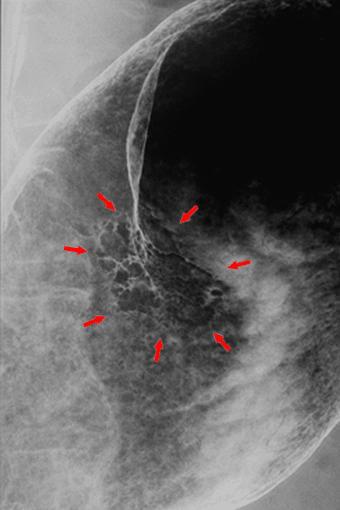

clasificación del pacienteTumor Epitelial Maligno/Adenocarcinoma

parte(separada por órganos)estómago(región)/cuerpo

método de exámenRayos X

clasificación ectoscópica de tumoresTipo 0(tipo superficial)/Tipo IIc(IIc+IIa)

diámetro mayor del tumor30 - 34

grado de penetraciónsm